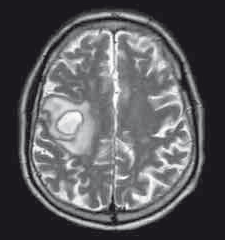

80岁男性,由于口齿不清和左侧面部下垂就诊。MRI检查前两图。初步诊断为急性脑梗死,患者接受阿司匹林和氯吡格雷治疗2天后出院。 16天后,患者由于左上肢麻木无力2天再次就诊。 既往史:高血压、高血脂,慢性阻塞性肺疾病,冠心病支架放置术后7年,右侧脓胸剥脱术8年。曾吸烟,无饮酒或违禁药物使用史。 家庭史:无神经系统疾病遗传史,亲属有心肌梗死及结肠癌患者。 体格检查:一般体格检查未见显著异常。神经查体显示患者言语流畅,但为构音障碍性言语,此外还存在吞咽困难、显著左侧面部下垂,多步骤命令执行困难。左侧上肢肌力减弱(近端3/5,远端4/5),精细动作协调性障碍,边距不良,轮替运动障碍。 辅助检查:患者的血象和炎症标记物均在正常范围内。颈动脉超声检查未见显著异常。MRI扫描见第三图。